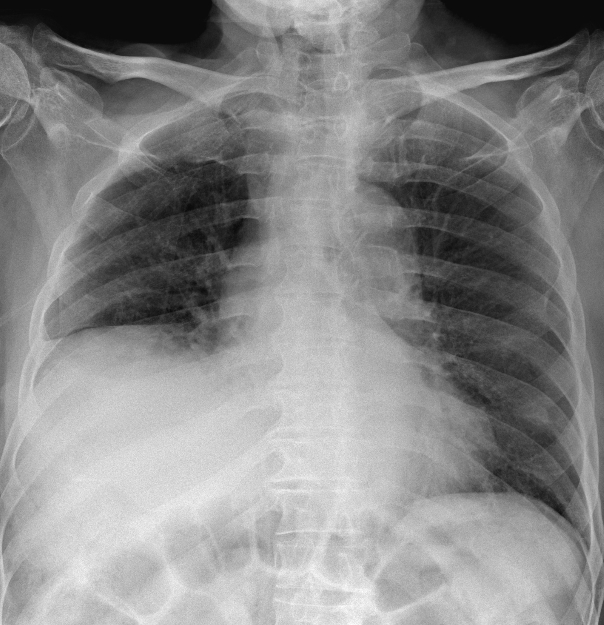

Radiografía de tórax: pérdida de volumen pulmonar con elevación de hemidiafragma derecho (imagen 1), no presente en previas (imagen 2). No claros infiltrados ni derrame pleural.